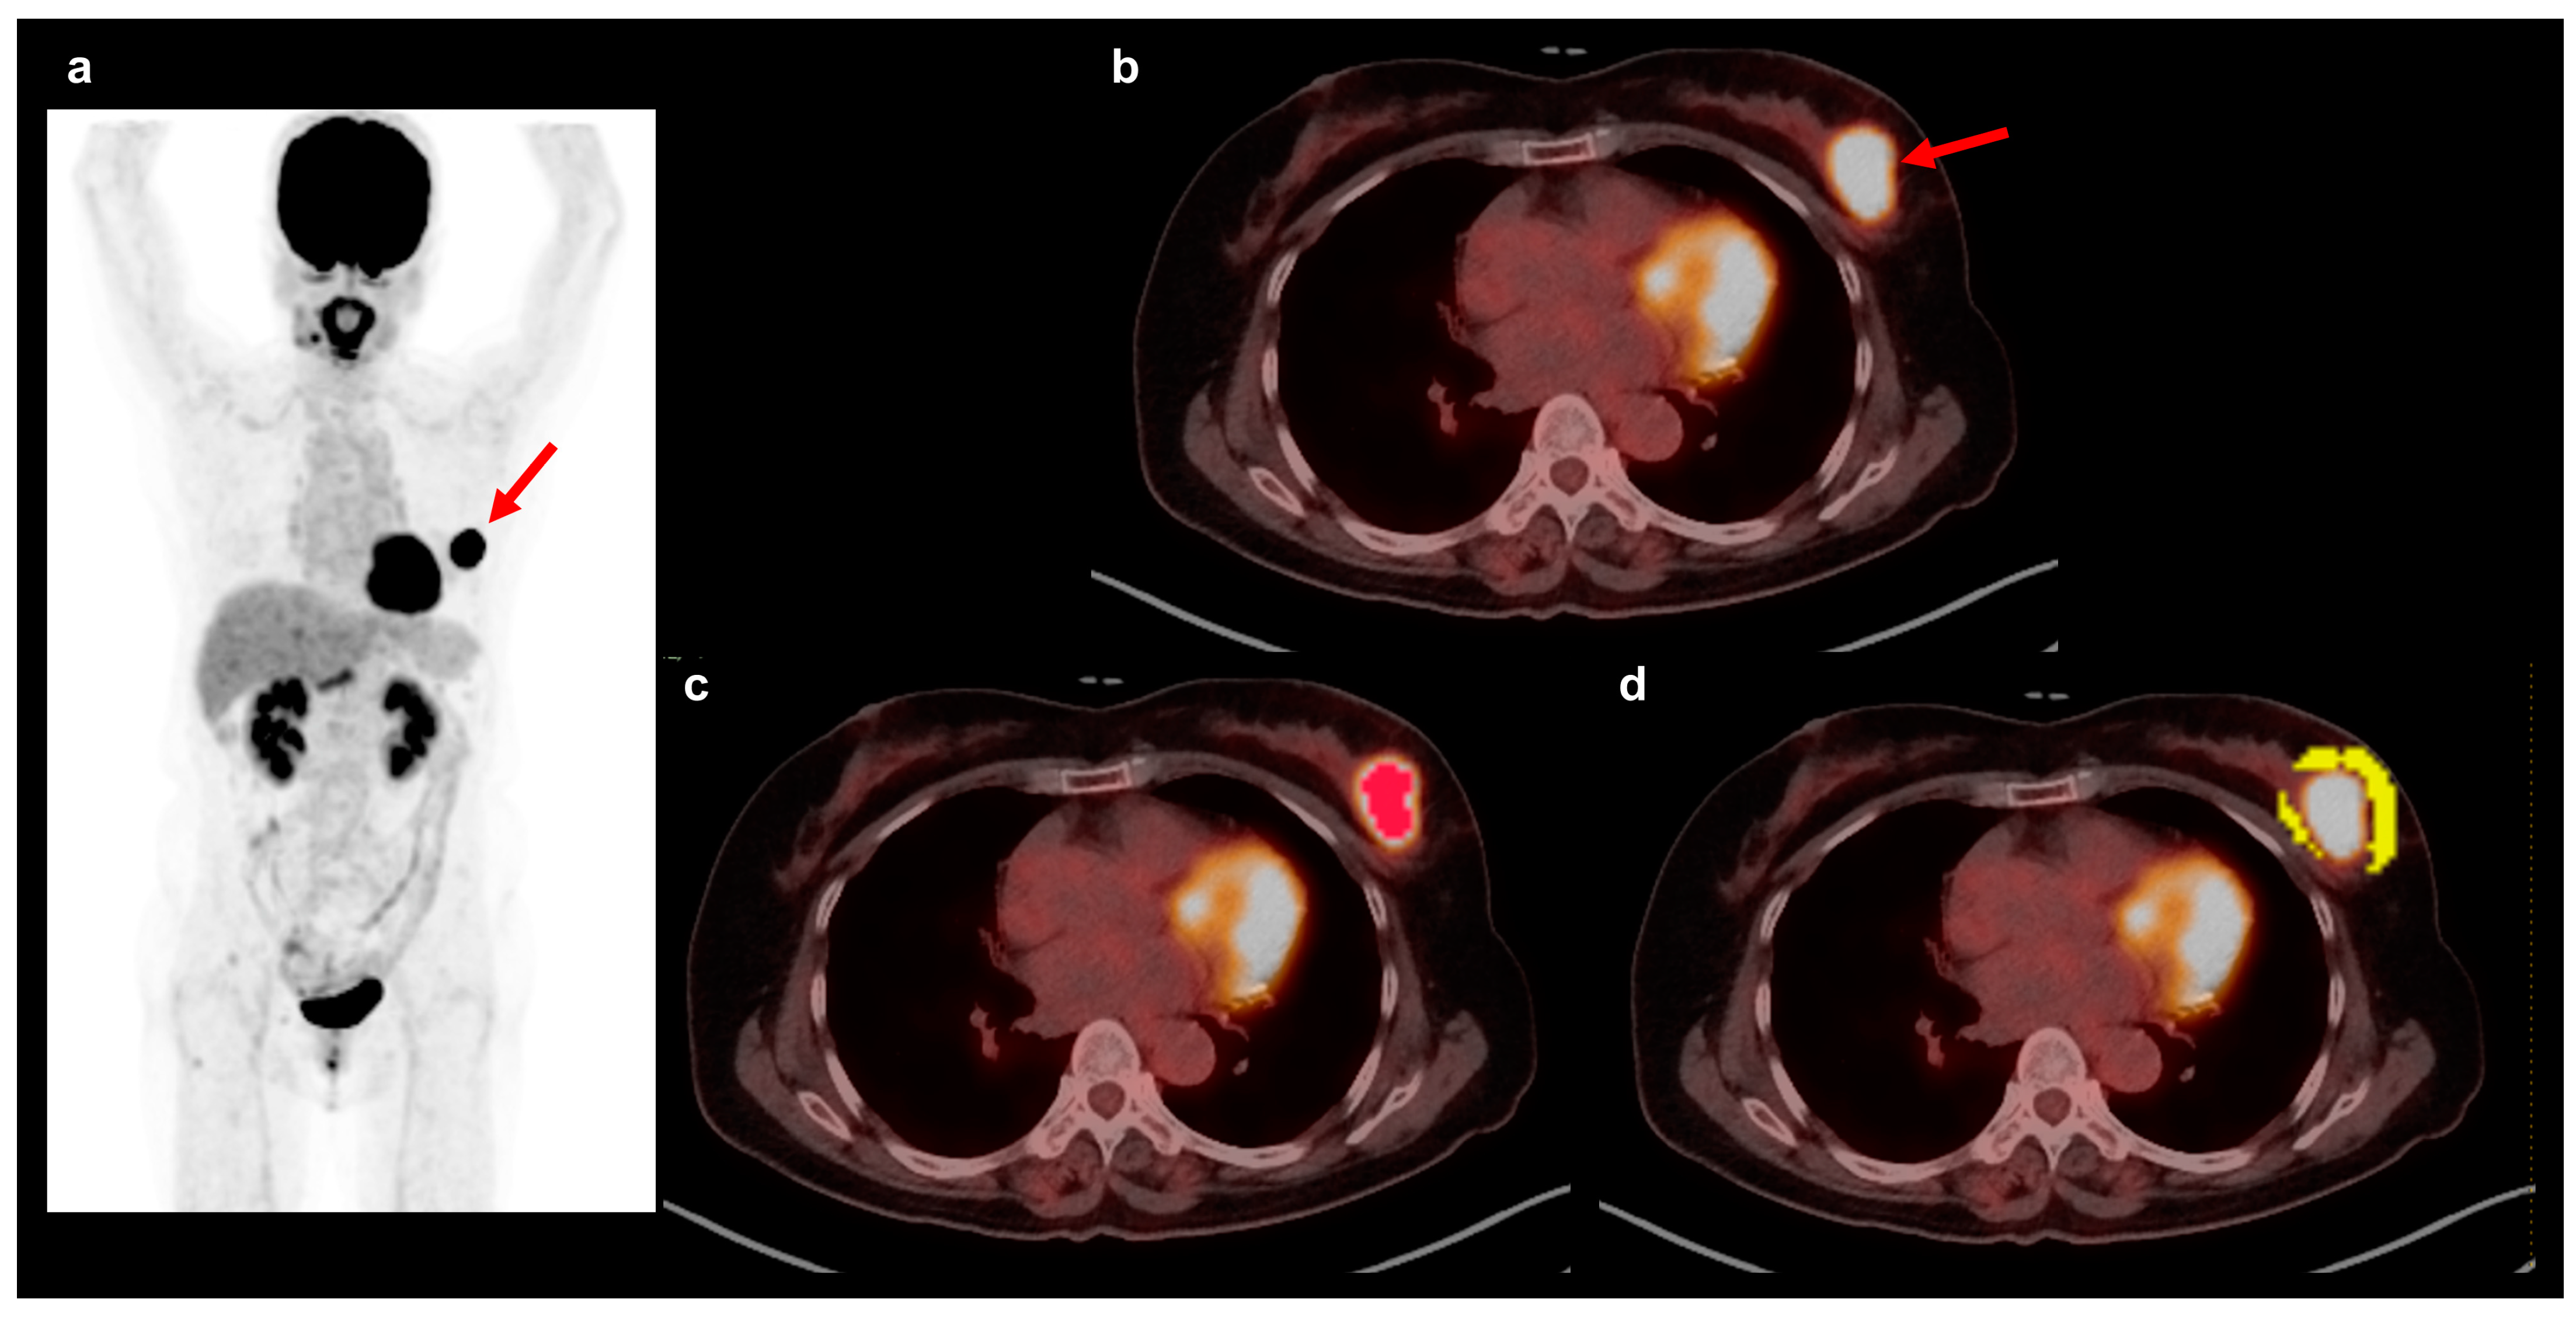

- Lee, J.W.; Kim, S.Y.; Han, S.W.; Lee, J.E.; Hong, S.H.; Lee, S.M.; Jo, I.Y. Clinical significance of peritumoral adipose tissue PET/CT imaging features for predicting axillary lymph node metastasis in patients with breast cancer. J. Pers. Med. 2021, 11, 1029. [Google Scholar] [CrossRef]